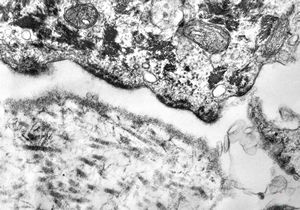

M, 22y. | epidermolysis bullosa - junctional type

M, 22y. | epidermolysis bullosa - junctional type, uncompletely separated basement membrane